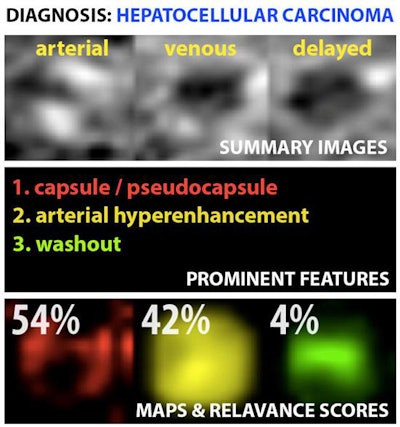

Example output of the Yale group's patent-pending "explainable" deep-learning system. In addition to providing a prediction (e.g., hepatocellular carcinoma), an explainability algorithm justifies the system's decisions with radiological features, feature maps, and relevance scores that contributed to its analysis. Image courtesy of Dr. Julius Chapiro.

Example output of the Yale group's patent-pending "explainable" deep-learning system. In addition to providing a prediction (e.g., hepatocellular carcinoma), an explainability algorithm justifies the system's decisions with radiological features, feature maps, and relevance scores that contributed to its analysis. Image courtesy of Dr. Julius Chapiro.The 494 liver lesions included six liver lesion types: simple cysts, hemangioma, focal nodular hyperplasia, HCC, intrahepatic cholangiocarcinoma, and colorectal carcinoma metastasis. These lesions were defined on T1-weighted MRI scans (arterial, portal venous, and delayed phase) and were divided into a training set of 434 lesions and a test set of 60 lesions. Next, the group compared the algorithm's performance on the test set with that of two board-certified radiologists.